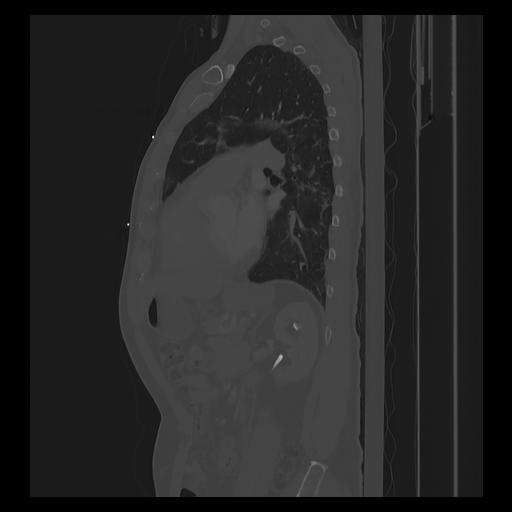

33 PULMON,CE,Sagittal,3.000,PULMON,Sagittal,